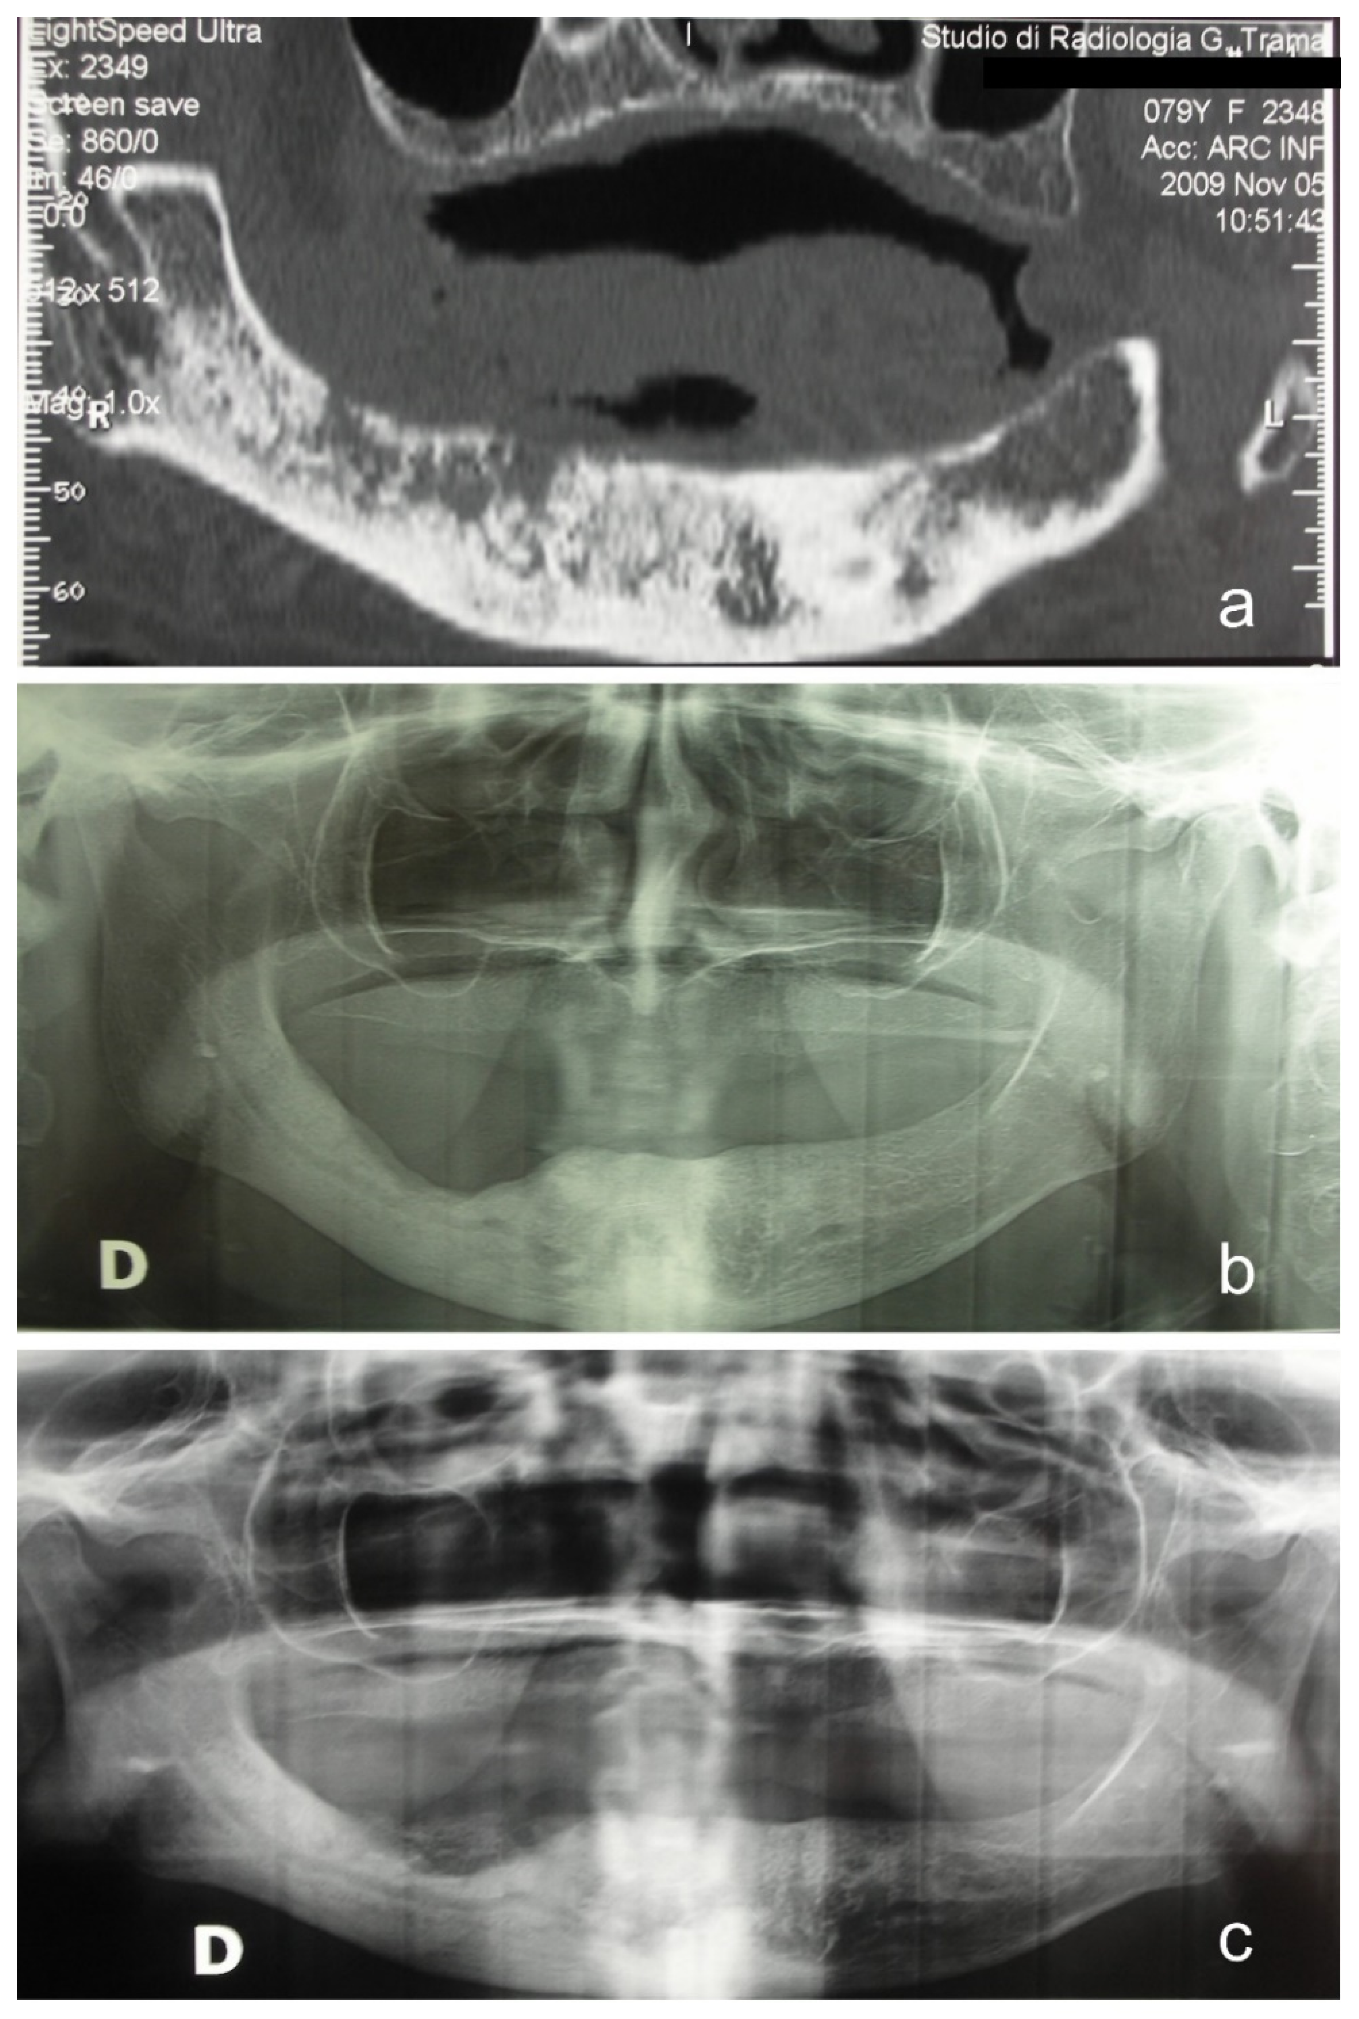

2. Materials and Methods

- Group A (n = 9)—patients who received sequestrectomy and autologous fat graft;

- Group B (n = 12)—patients who received sequestrectomy alone.

Treatment Protocol